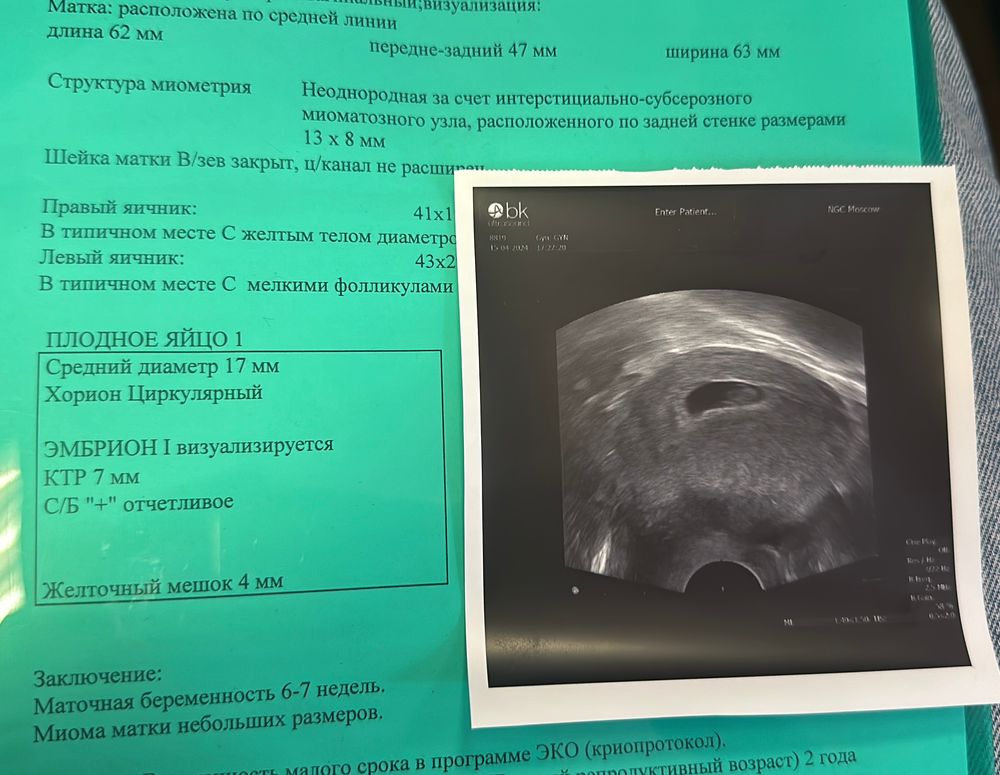

Неправильной формы ПЯ (5,4 недели) 21 дпп

Всем привет, 6я неделя, сегодня было первое узи, по узи ПЯ деформировано, размер ПЯ 19, размер жм 2 мм, врач сказал тонус матки, но без симптомов, может быть особенность строения матки. Пить валерианку, не нервничать, побольше отдыхать. У кого было так же?

Здравствуйте, сделали УЗИ сейчас, ПЯ тоже неправильной формы(( ПЯ 12, ЖМ 2,8 эмбриона нет(( В итоге, вижу у вас все хорошо с беременностью?